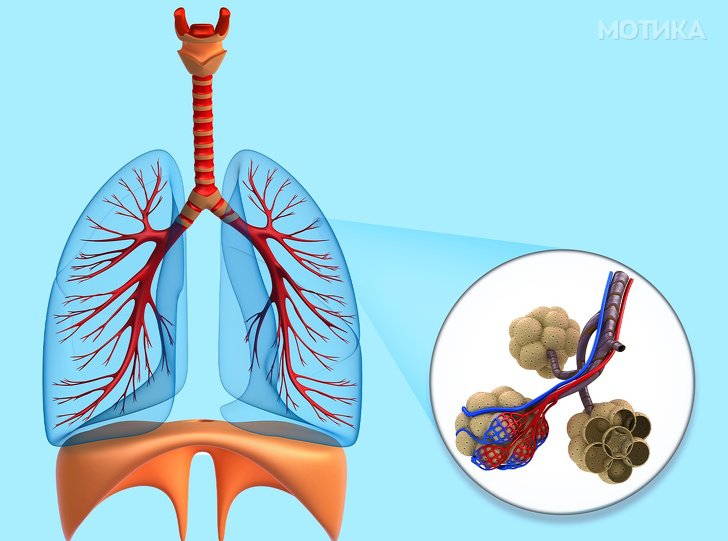

3. Белите дробови

- Белите дробови се толку лесни што можат да пливаат на површината на водата.

- Секој ден околу 10.000 литри воздух поминува низ белите дробови.

- Белите дробови имаат рецептори за вкус кои се способни за откривање на горчливи вкусови.

- Белите дробови играат важна улога кога станува збор за зборување или дури и само правење звуци.